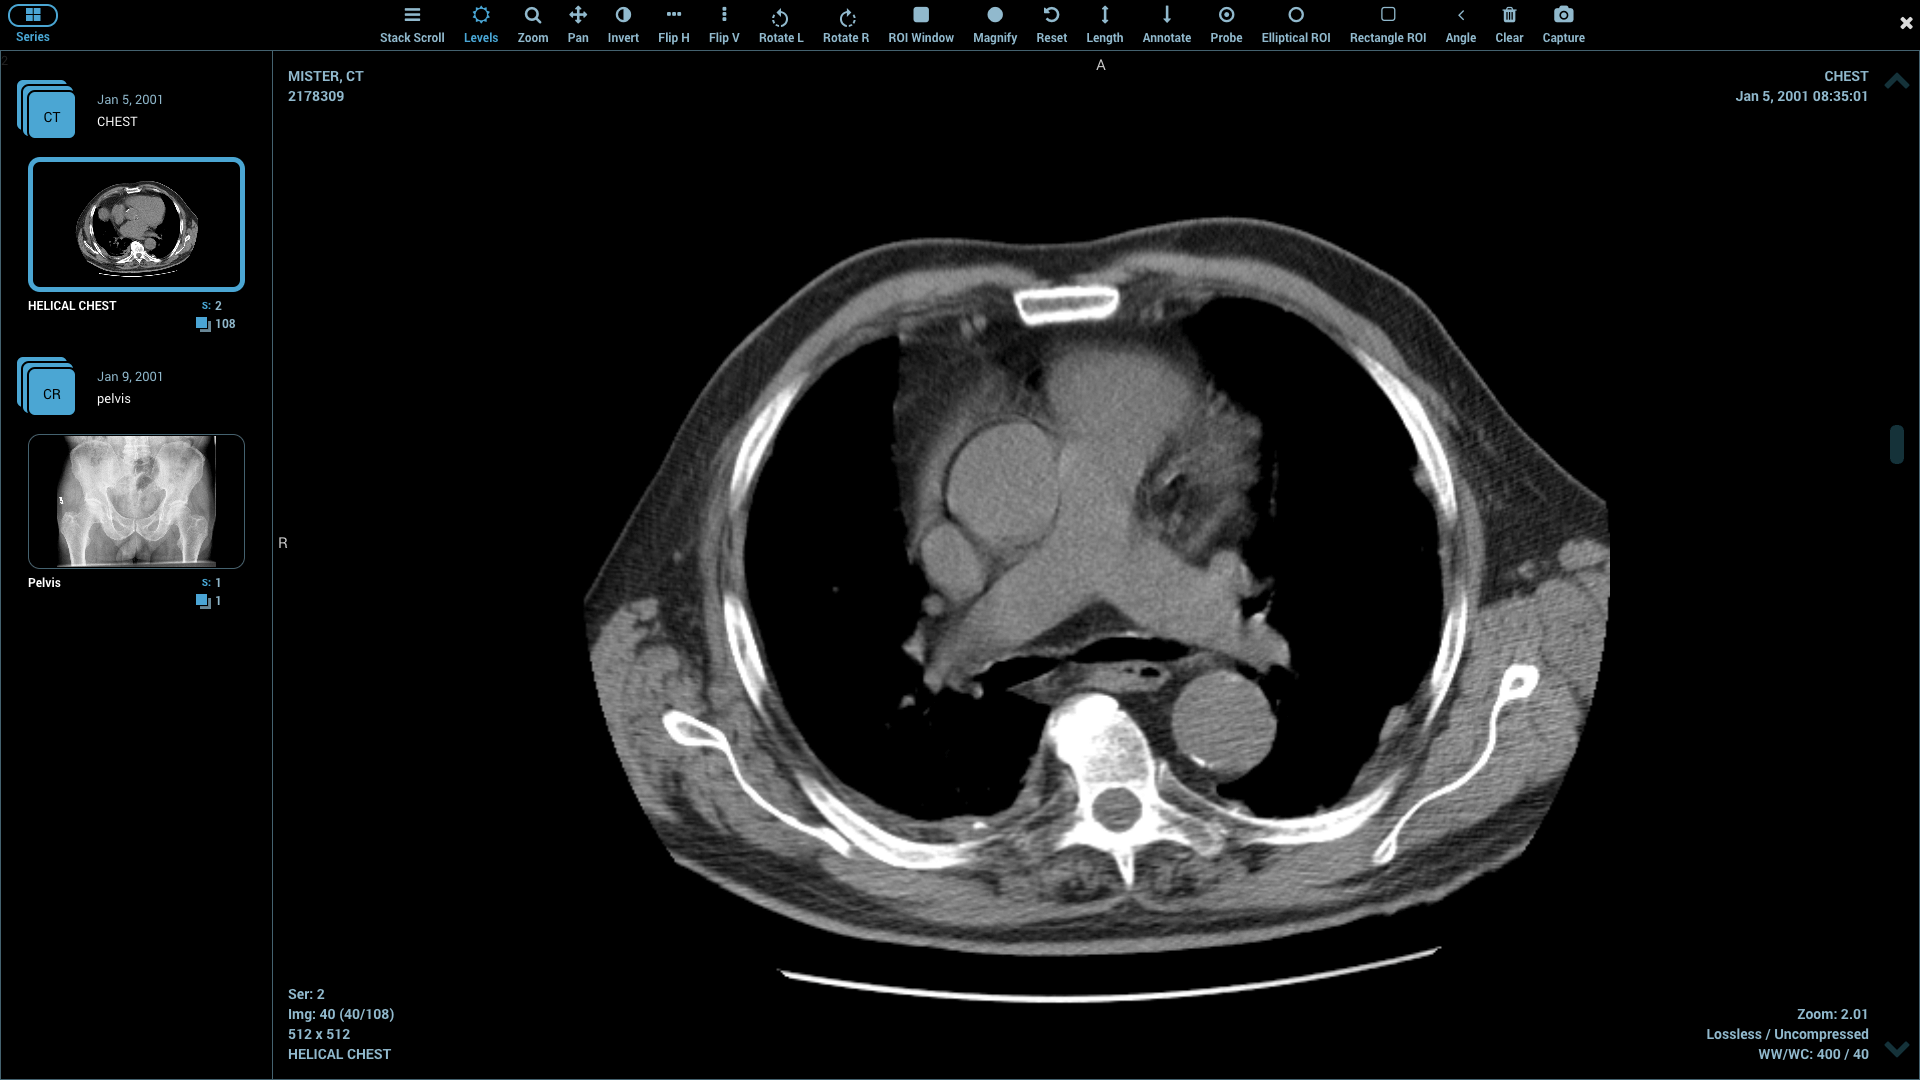

| 15. | Athena | Windows 10 | Available but in paid version | Y | Y | Y | Y | 500 MB | Intel core/ 8 GB RAM, DirectX Version 10 | Free only for one month |